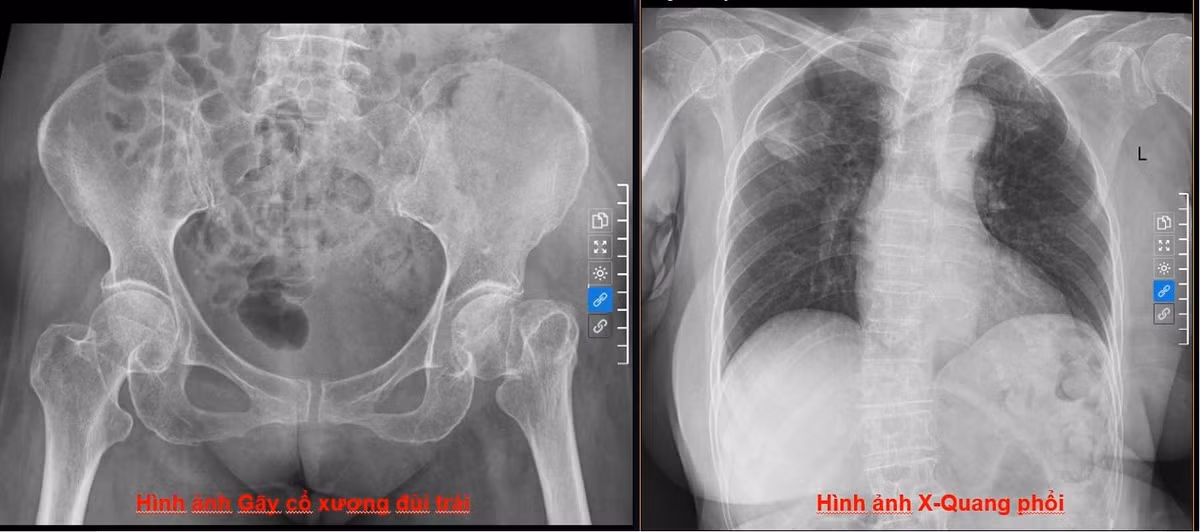

Hình ảnh phim chụp X-Quang gãy cổ xương đùi trái và chụp X-Quang phổi của bệnh nhân